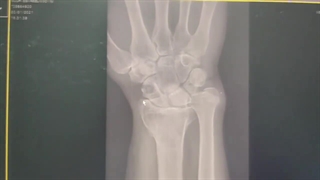

فیلم از جراحی مچ دست

دکتر نیما یگانه متخصص جراحی ارتوپدی